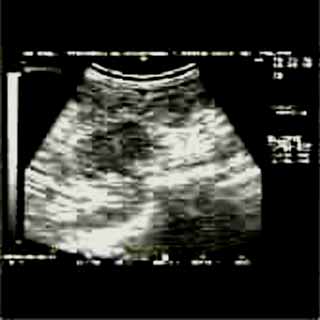

Για την καλλίτερη απόδοση της εξέτασης απαιτείται κεφαλή linear τουλάχιστον 7,5 ΜΗΖ. Ωστόσο και με κεφαλές 3,5 και 5 ΜΗΖ μπορεί κανείς να έχει καλά αποτελέσματα.

Oι τελευταίες 4 απεικονίσεις έγιναν με ειδικό για μαστό ηχοβολέα linear, εναλλασσομένης συχνότητος 7,5-10ΜΗΖ.